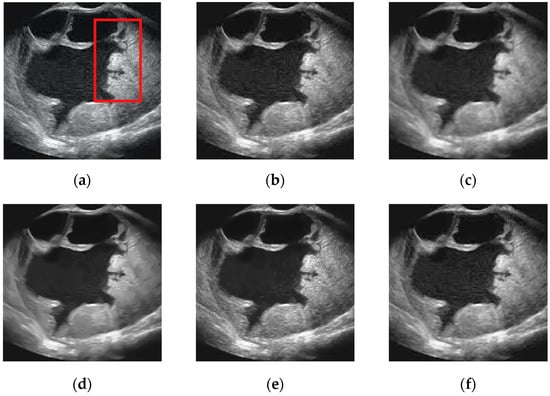

5.2. Real Ultrasound Image Denoising Experiment

5.2.2. Experimental Results